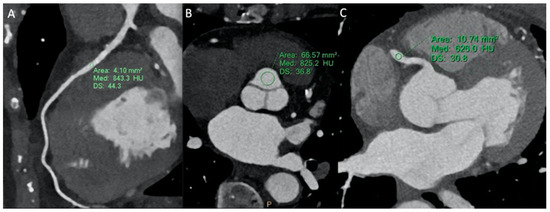

3.2.1. CCTA